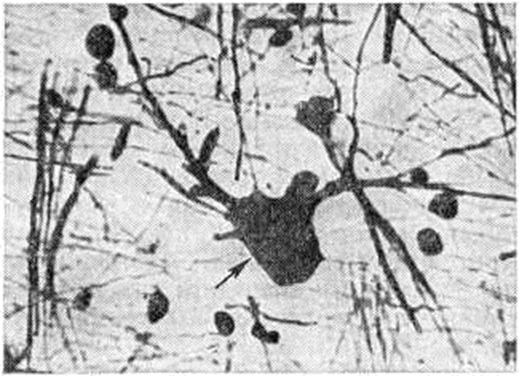

В буграх, расположенных в белом веществе полушарий головного мозга и мозжечка, обнаруживают единичные крупные атипичные клетки с пузырьковидным ядром, а также гнездные скопления клеток с гиперхромными ядрами и сморщенной цитоплазмой (рисунок 3). Опухолеподобные образования в мозге больных Туберозный склероз содержат в одних случаях крупные округлые клетки, похожие на атипичные нейроны, в других — округлые или веретенообразные клетки с овальными либо удлинёнными ядрами или многоядерные клетки. Эти образования по гистологический строению сходны с невриномами (смотри полный свод знаний), субэпендимарными астроцитомами (смотри полный свод знаний), эпендимомами (смотри полный свод знаний). Узлы, обнаруживаемые в глазном яблоке, чаще всего являются глиомами. Описаны также очаговые обызвествления в сосудистой оболочке глазного яблока, её ангиомы (смотри полный свод знаний), пороки развития глаза.